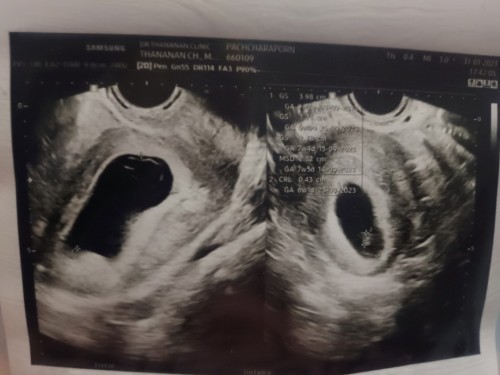

วันนี้ครบ 8wไปหาคุณหมอเพื่อฝากครรภ์คุณหมอแจ้งว่าพบถุงตั้งครรภ์แต่ยังไม่เจอน้องแล้วก็ไม่ใช่ท้องลมอีก 2 สัปดาห์นัดอัลตร้าซาวด์อีกรอบว่าจะเจอน้องไหม? มีบ้านไหนเป็นแบบนี้บ้างไหมคะ? เรามีโอกาสที่จะได้เจอน้องไหม?🥺

เหมือนกันค่ะแต่ของแม่บ้านนี้7สัปดาร์2วันเจอเเต่ถุงน้ำคร่ำแต่ไม่เจอตัวน้องเลยนัดตรวจอีกสองอาทิตคะกังวลเหมิอนกัน🥺🥺